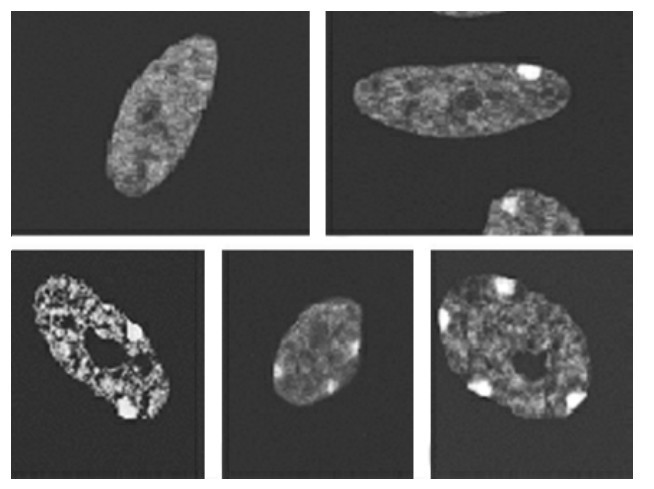

1.X染色体的失活 Xp和Xq上均有很多区域或基因在性别决定中起着特殊的作用。女性有2条X染色体,男性只有1条,但女性X染色体的基因产物并未比男性多1倍。对此,英国遗传学家Mary Lyon在1961年首先提出了“X失活假说”,或称“Lyon”假说,其要点是:①在间期细胞核中,女性的2条X染色体中,只有1条X染色体有转录活性,另外1条X染色体无转录活性,呈固缩状,形成X小体或Barr小体。这样,在含XX的细胞和XY的细胞中,其X连锁的基因产物数量就基本相等,称为剂量补偿(dosage compensation)。不论细胞内有几条X染色体,只有1条X染色体是具有转录活性,其余的X染色体均失活、固缩,形成X染色质。因此,一个细胞中所含的X染色质数目等于X染色体数目减1。怀疑有X染色体数目异常时,可以通过用性染色质检查做出初步诊断。例如,细胞核内X小体数目在正常男性和一个X女性患者为0,在正常女性和XXY男性患者中为1,XXX患者则为2(图10-3)。②失活发生在胚胎早期,受精后约第3天(桑椹期)16-24细胞开始,第1周末完成。③失活是随机的,即失活的X染色体既可来自父亲,也可来自母亲,但一个细胞某条X染色体一旦失活,由该细胞繁衍而来的子细胞都具有同一条失活的X染色体。换句话讲,失活是随机的,一旦形成,保持不变。

图10-3 细胞分裂间期的X小体